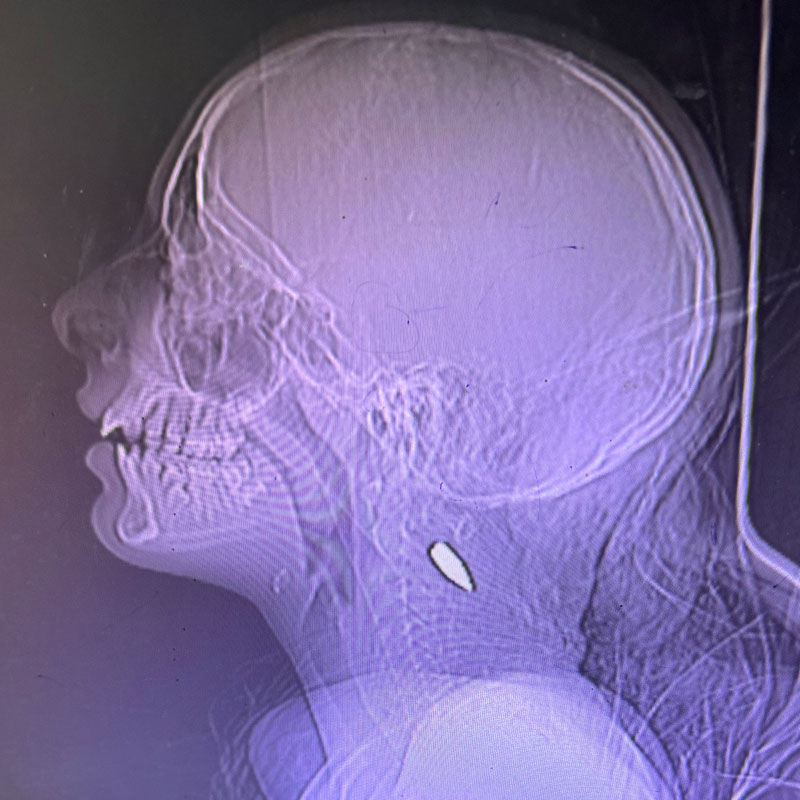

Ces radiographies montrant des enfants de Gaza avec des balles dans le cou ou la tête ont été partagées par le Dr Mimi Syed, qui a travaillé à Khan Younis du 8 août au 5 septembre. Elle a expliqué : « J’ai pris en charge de nombreux jeunes patients, pour la plupart âgés de moins de 12 ans, atteints d’une balle dans la tête ou dans la poitrine, sur le côté gauche. En général, il s’agissait d’une seule balle. Les enfants arrivaient soit déjà morts, soit dans un état critique, et mouraient peu après leur arrivée. »